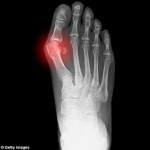

מחלת השיגדון (גאוט), אשר נקראה בעבר גם “מחלת המלכים” היא מחלה שבה, בגלל הפרעה בחילוף החומרים, מצטברת חומצת שתן בדם (חומצה אורית) ואז שוקעת כגבישים במפרקים בגוף וגורמת לדלקות קשות. הסיבה לשיגדון קשורה גם לאלכוהול ולמזון מסוים עשיר בפורינים כמו אפונה, דגים, פטריות ועוד (ולכן נקראה “מחלת המלכים”), אך התברר שהגורם העיקרי לה הוא גנטי… המשך הקריאה